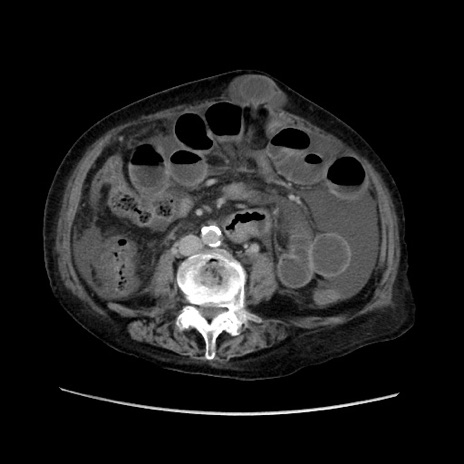

症例31(横断像)

【症例】80歳代 女性

【主訴】腹部膨満感

【現病歴】他院にて肝硬変にてフォロー中。1週間前から便秘、腹部膨満感、臍部腫瘤あり受診となる。

【既往歴】肝硬変

【身体所見】腹部膨隆あり、皮膚変化なし、疼痛なし。

【データ】WBC 4600、CRP 0.25